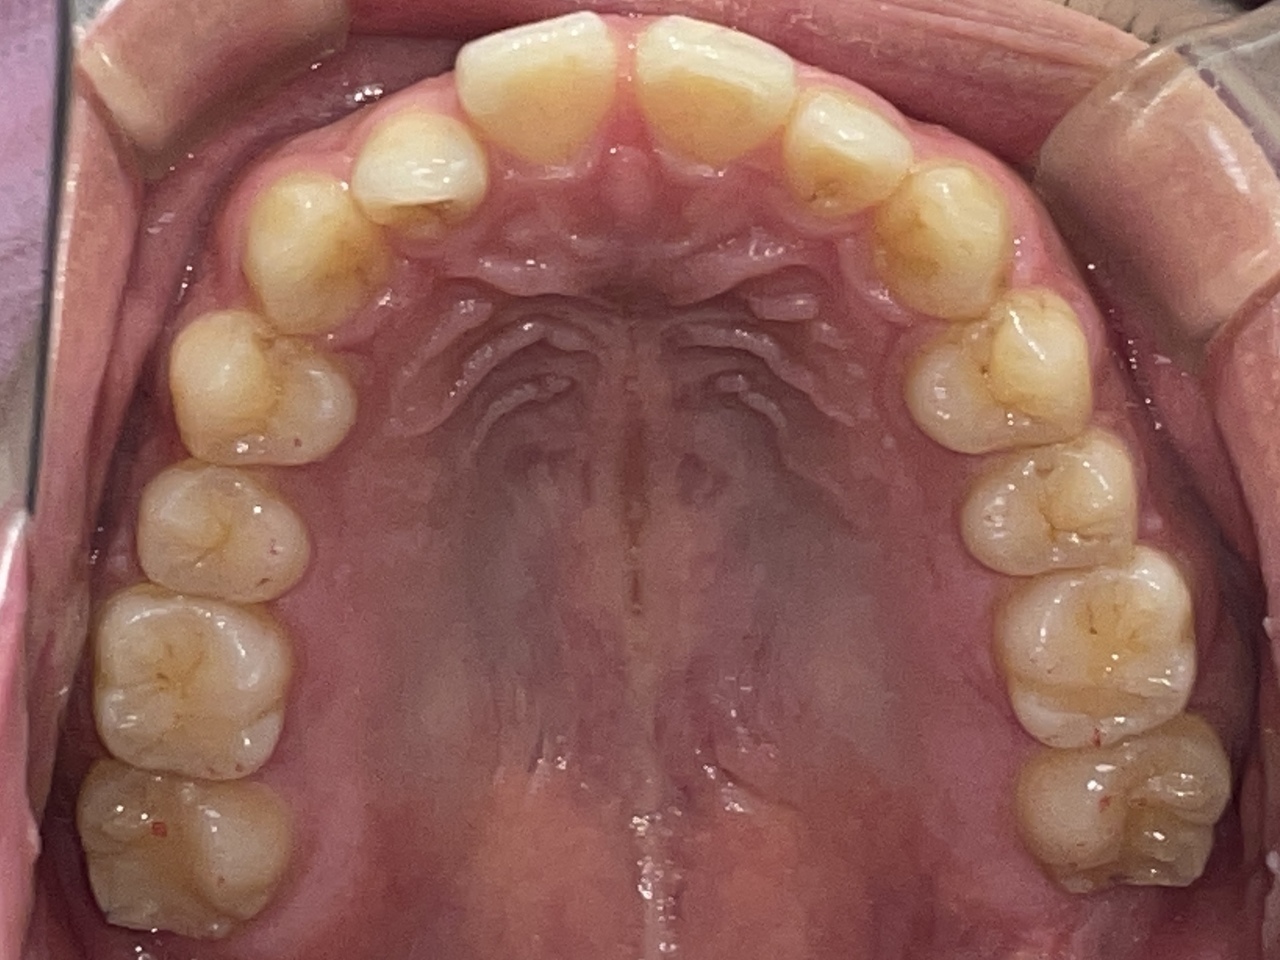

Before

After

矯正の種類 / invisalign GO

年齢・性別 / 20代男性

主訴  /  上顎前歯の空隙、上下顎前歯の叢生

治療期間 / 24ヶ月

費用 / 簡易検査 5,000円(税別) 精密検査 30,000円(税別)

両顎マウスピース 450,000円(税別) 両顎リテイナー料 40,000円(税別)

※マウスピース交換時別途調節料5,000円(税別)

副作用 / 口内炎・歯の移動に伴う痛み・知覚過敏 ※数日で収まる場合が多いです

リスク / 後戻り防止の為、夜のみマウスピースで保定を指示